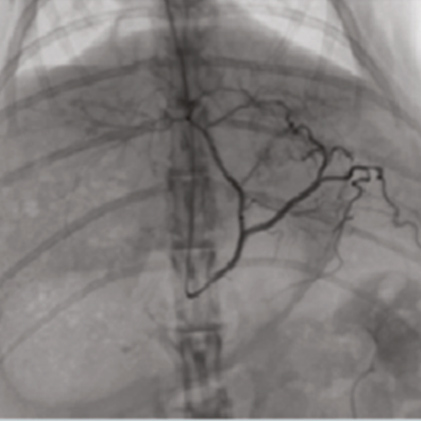

DSA(Digital Subtraction Angiography) helps various clinical diagnosis and procedures through the vessel image information after injecting contrast medium.